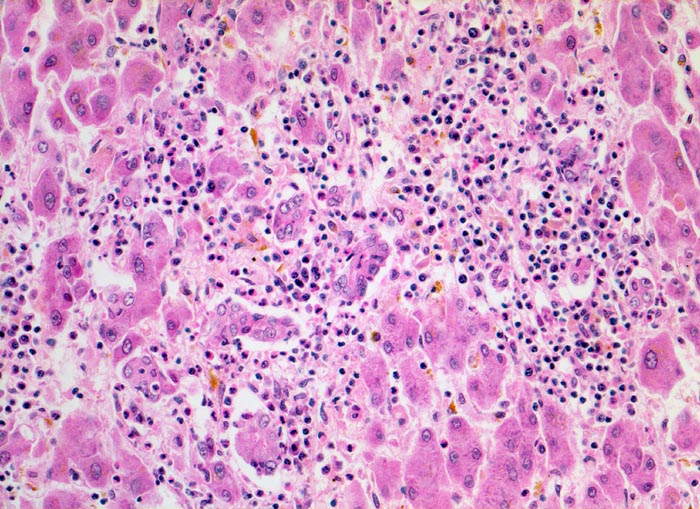

Das histologische Bild der akuten Hepatitis vom Virustyp ist gekennzeichnet durch eine lobuläre Entzündung bei fehlender portaler Fibrose und nur geringer entzündlicher Infiltration der Portalfelder. Es finden sich ballonierte Hepatozyten, Apoptosen (> 1164) und fleckige Nekrosen. Perivenuläre Nekrosen, Brückennekrosen oder konfluierende multilobuläre Nekrosen und eine läppchenzentrale Cholestase können vor allem in klinisch fulminant verlaufenden Fällen nachgewiesen werden. Zahlreiche Makrophagen, welche Diastase-PAS positives Zeroidpigment (> 4319) von phagozytierten nekrotischen Hepatozyten enthalten, zeugen im subakuten Stadium von einer abgelaufenen akuten Hepatitis mit Parenchymnekrosen. Eine Unterscheidung der verschiedenen Typen der viralen Hepatitis und einiger Formen medikamentöser Hepatitiden gelingt rein morphologisch aufgrund des unspezifischen Bildes meist nicht. Für eine ätiologische Klassifizierung sind zusätzliche klinische Angaben erforderlich (Anamnese, Medikamente, Serologie).

• Regelrechte Läppchenarchitektur.

• Lobuläre gemischte Entzündung.

• Ansammlungen zeroidbeladener Makrophagen innerhalb von Parenchymnekrosen (abgebaute fleckförmige Nekrose).

• Apoptosen (hypereosinophile abgerundete Leberzellen).

• Portale gemischte Entzündung.

• Fehlende Fibrose.